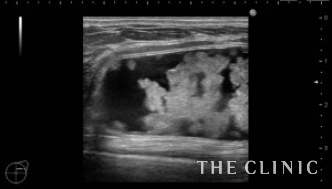

1年前に他院にて脂肪注入による豊胸を受けられた方です。2ヵ月程前にしこりに気付き、除去して欲しいとのことで当院へご来院されました。エコー所見です。両側とも乳腺下にあり、右10㎝、左5㎝の被膜に包まれた混合性(充実成分+嚢胞成分)のしこりです。この他に、1㎝のオイルシストが左に確認出来ました。